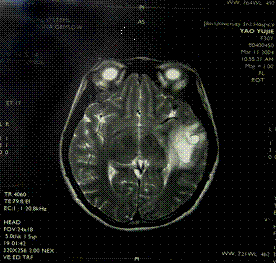

原發性腹膜癌患者,女,66歲。於2005年3月15日出現腹脹、左下腹痛、腰部增粗,3月30日到廣州紅十字會醫院就診,B超提示中至大量腹水,擬腹水查因收入院。入院後做盆腔CT提示盆腔大量積液,不排除由左側卵巢腫瘤所致。腹腔穿刺腹水塗片找到乳頭狀腺癌細胞,血CA125 387.70u/ml,CA199 19.9u/ml,肝、膽、脾、泌尿系B超無異常,結腸鏡示直腸下段炎,胃鏡及病檢示胃黏膜慢性炎,未見癌。因診斷不明於4月15日入院。自發病來,體重減輕3.5kg,胃納較差,大小便正常。既往史無特殊。1993年絕經,孕3產1。入院查體:血壓110/80mmHg,脈搏88次/min,心肺聽診正常,腹膨隆,腹圍93cm,移動性濁音陽性,腸鳴音3次/min,雙下肢無水腫,外陰、陰道正常,宮頸光滑,宮體及附屬檔案捫診欠清,左附屬檔案區壓痛。入院後於2005年4月19日在腰硬聯合麻醉下行剖腹探查術。術中見大量腹水,盆腹腔臟器、腹膜廣泛受累,大網膜增厚,團塊狀。子宮萎小,雙卵巢2.5cm×1.5cm×0.8cm,雙輸卵管增粗,腸管、腸系膜、卵巢表面、子宮漿肌層、輸卵管表面均有散在粟粒狀至乳頭狀瘤結節,質脆,行腫瘤減滅術(雙附屬檔案+部分大網膜切除術),術中置入Carbo 0.3g,5-FU 1.0g,4月25日、26日予Carbo 0.2g,FUDR 1.5g靜滴化療,2005年4月28日好轉出院。術後病理:瘤細胞CEA陽性,MC間皮標記細胞陽性,CR陽性,EMA陽性,病變符合原發性腹膜腺癌。診斷:原發性腹膜腺癌晚期。